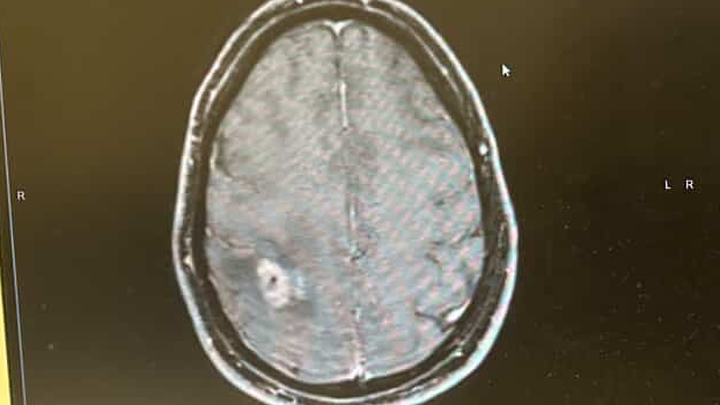

After months of being ignored and dismissed - on November 20, 2025, I had two focal seizures and finally got the news nobody wants. I have a brain tumor that needs removal ASAP.

So, on December 8, 2025, my amazing neurosurgeon at Mass General Hospital will literally crack my skull and try to evict this mutant in my head.

Unfortunately, even with this, my prognosis could be as little as two years. This tumor could be partially removed, but it will return. It is on my motor belt, so I am already partially paralyzed on my left side.